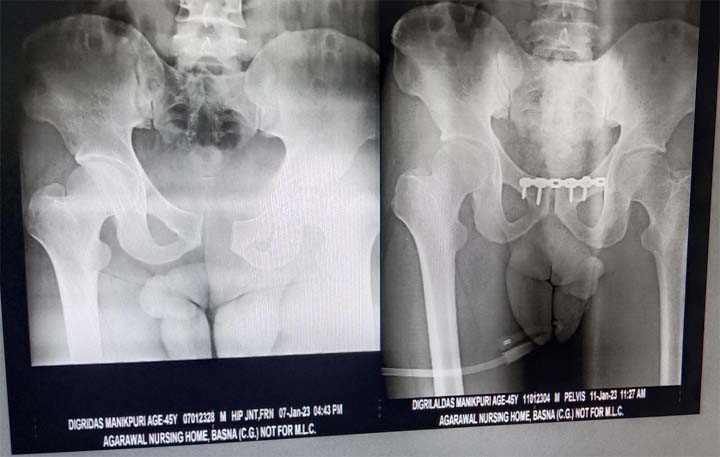

बसना: सड़क दुर्घटना में टूट गया था कमर की हड्डी,अग्रवाल नर्सिंग होम के टीम डॉ. संदीप सराफ ने हड्डी को जोड़ा

बसना: अग्रवाल नर्सिंग होम बसना के चिकित्सकों के सराहनीय प्रयास से डिग्री दास मानिकपुरी ग्राम बरोली का कमर की हड्डी को जोड़ा गया सड़क दुर्घटना में टूट गया था कमर की हड्डी

चिकित्सकों के सराहनीय प्रयास से डिग्री दास मानिकपुरी ने दो ही दिनों में चलना शुरू कर दिया.इलाज आयुष्मान कार्ड द्वारा निःशुल्क इलाज हुआ